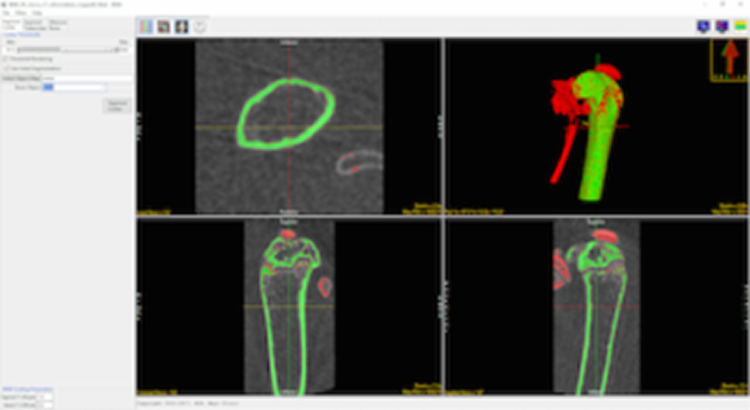

Cortical Bone Segmentation

Once the image data is loaded the BMA add-on will conduct a preliminary segmentation which will allow the module to identify the cortical shell, cortical pores and trabecular tissue regions.